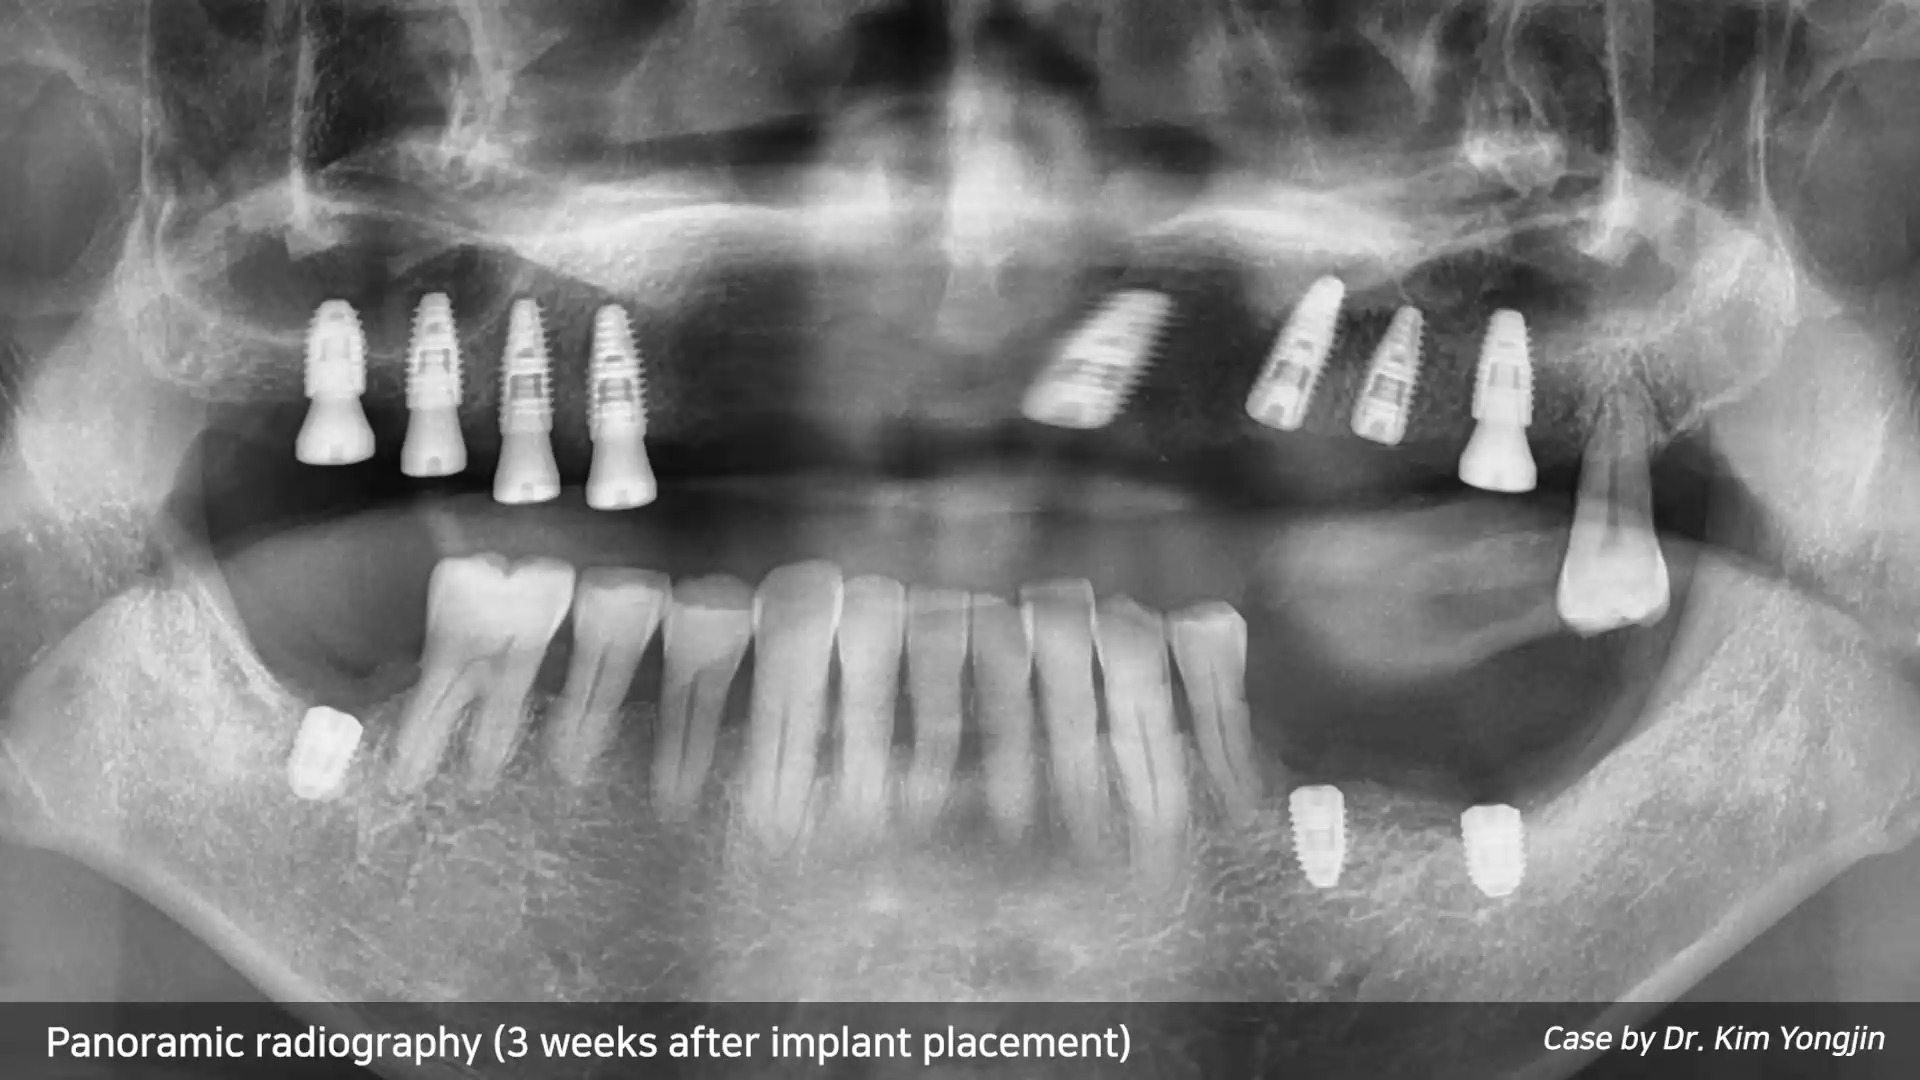

1 2 3 4 8